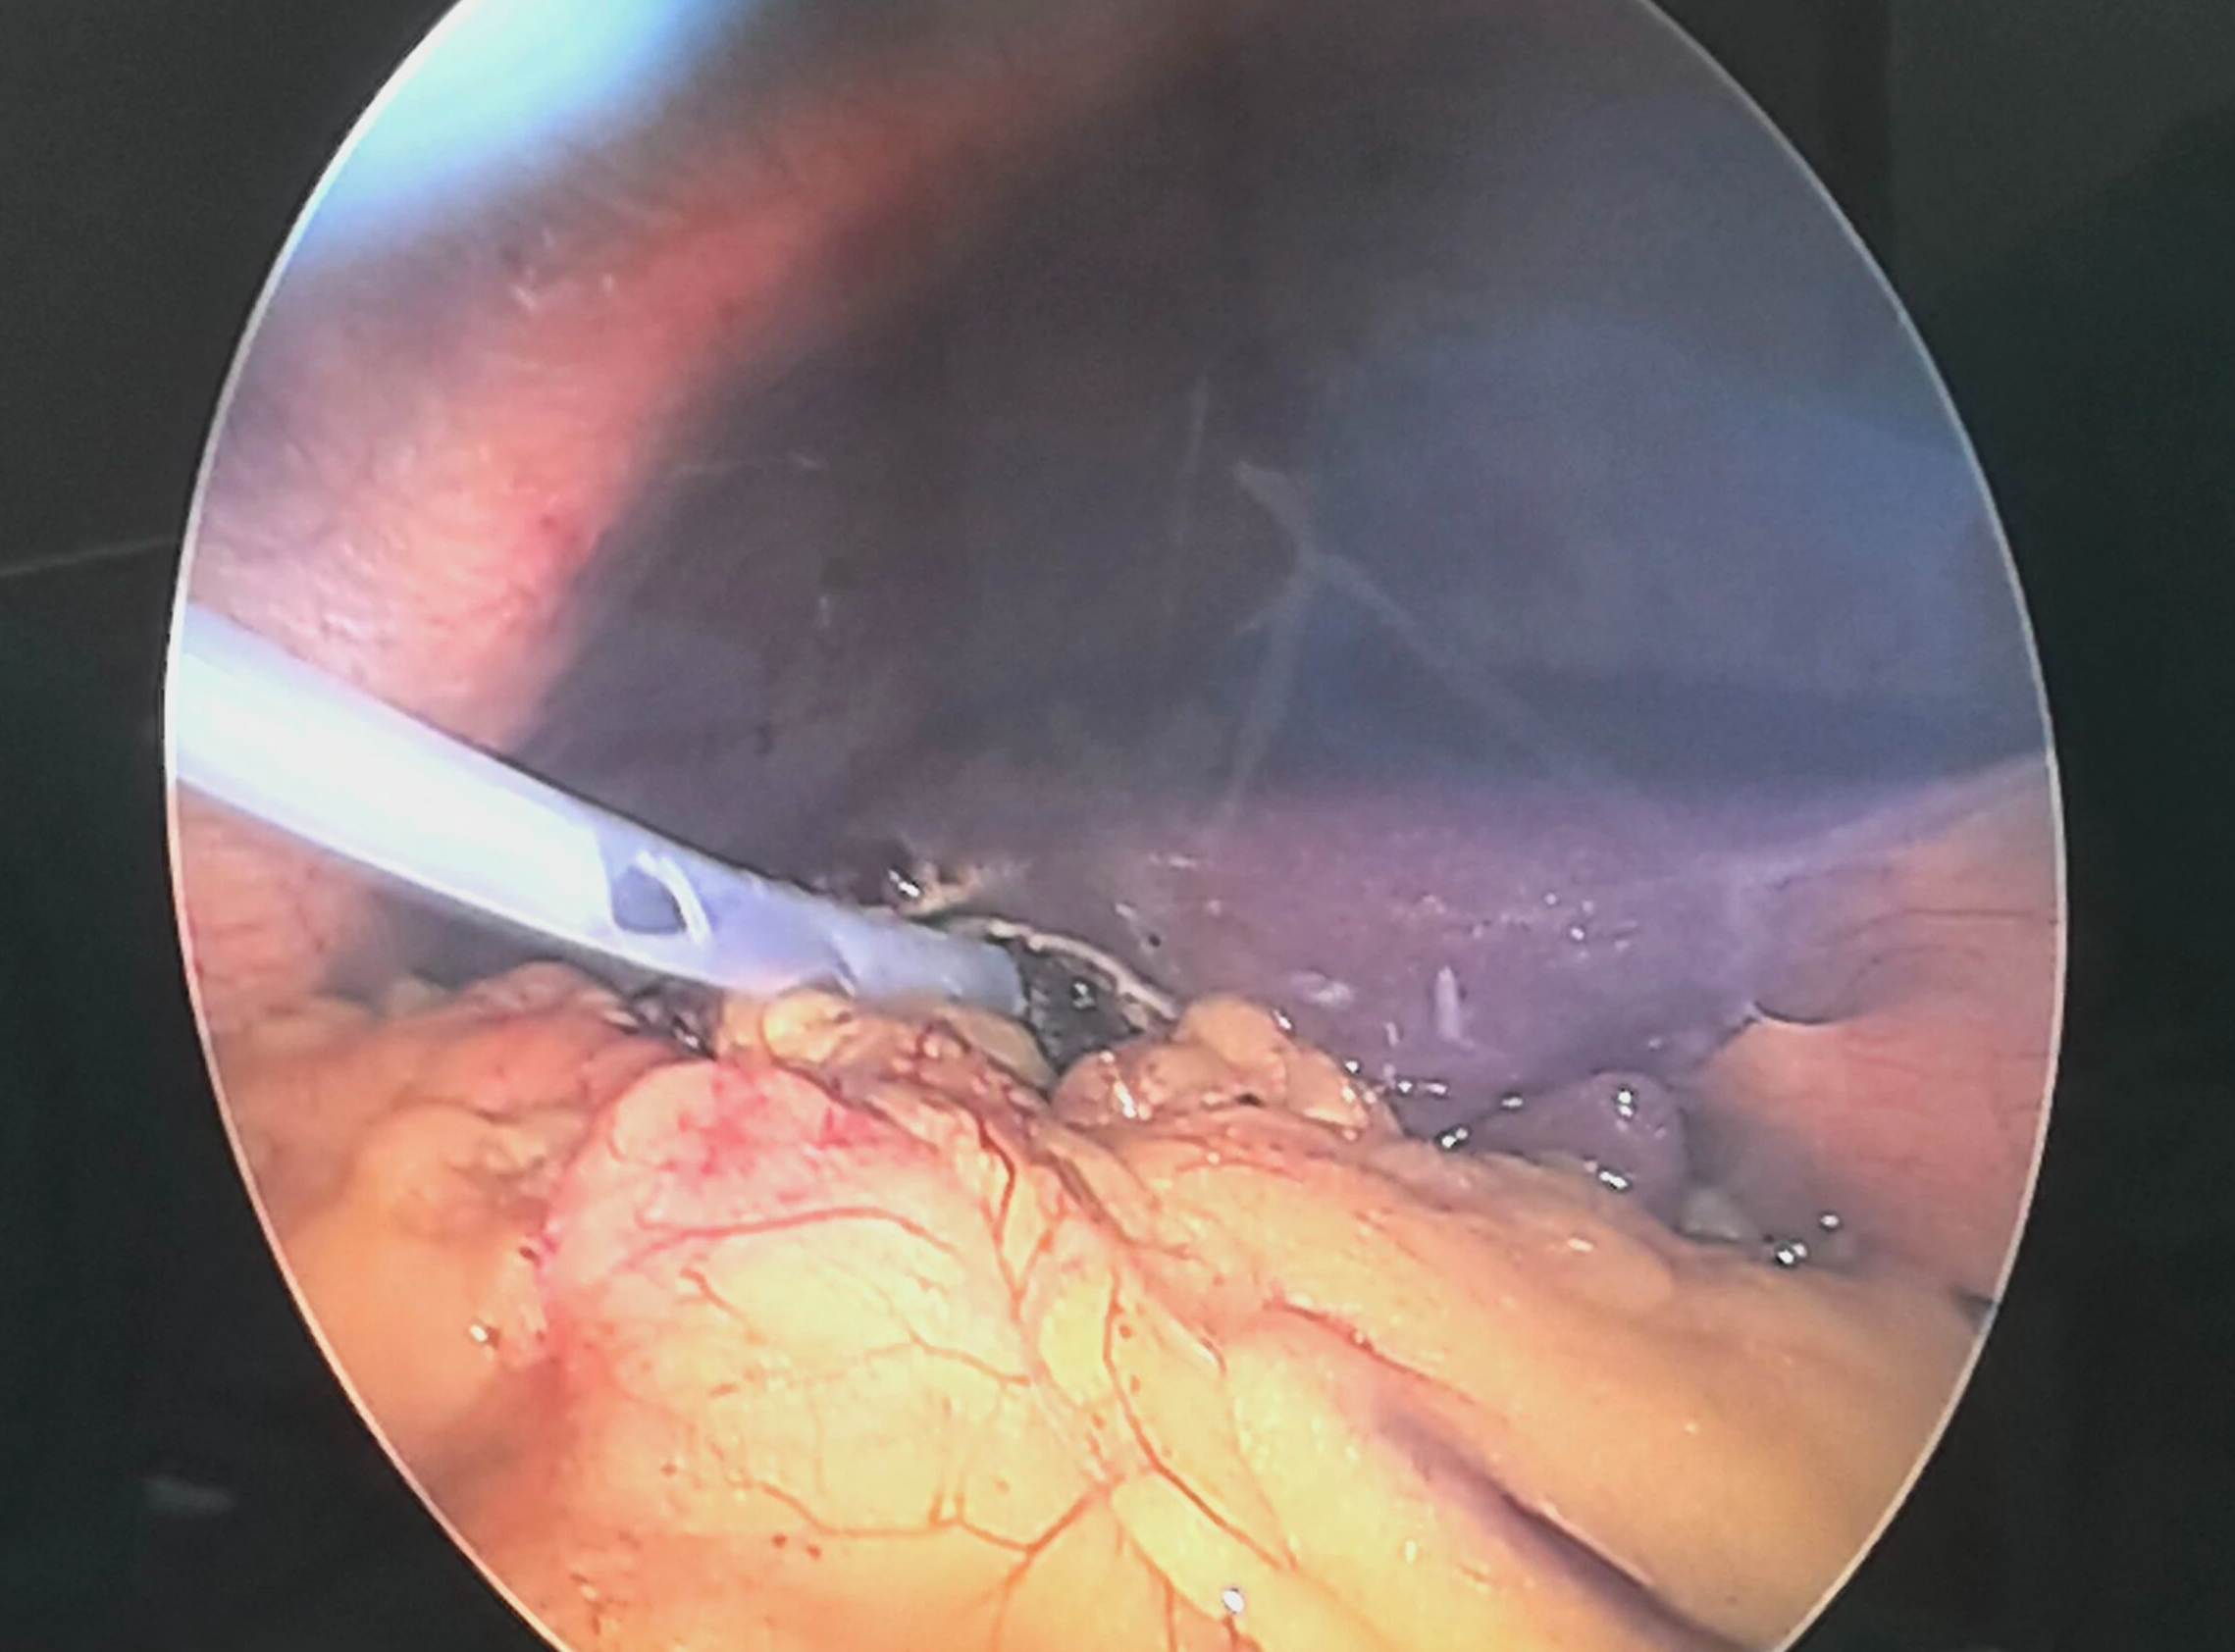

经完善检查,明确诊断并排除手术禁忌后,由董亚东教授与我院外科团队紧密协作,为马大爷成功实施了“经腹腔镜胆囊切除术”。手术过程顺利,凭借精准的微创操作,患者创伤小、出血少。术后,在马大爷的积极配合及医护人员的精心照料下,恢复迅速,状态良好,解决了困扰多年的病痛。

河南省人民医院肝胆外科董亚东教授联合我院外科团队为患者行腹腔镜胆囊切除术

经腹腔镜胆囊切除术后